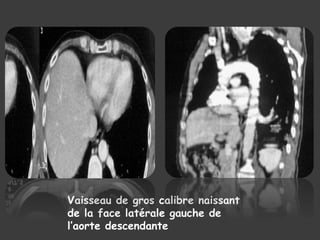

LE SCANNER THORACIQUE

 TDM+ PDC ====> EXAMEN DE CHOIX

Artère naissant du bord

latéral gauche de l’aorte

destinée au LIG

Masse kystique du LIG

avec hypovascularisation

Vaisseau de gros calibre naissant

de la face latérale gauche de

l’aorte descendante